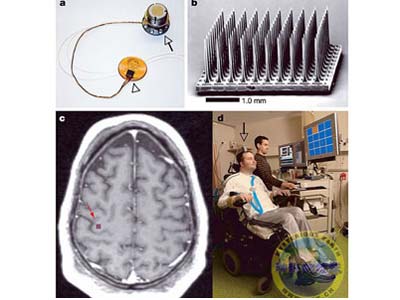

Theo giới thiệu của nhóm nghiên cứu Đại học Michigan, dây thần kinh nhân tạo được làm bằng các sợi nhựa dẫn điện pedot, một đầu được kết nối với hệ thần kinh của người bệnh, một đầu nối với đầu chân tay giả.

Sợi nhựa dẫn điện pedot có khả năng truyền tín hiệu thần kinh giữa các chi giả và não bộ với tốc độ phản ứng nhanh gấp 2 lần tế bào thần kinh của người, nhờ vậy khả năng truyền dẫn tín hiệu nhanh hơn 10 lần so với các kim loại thường dùng, đồng thời còn kích thích tế bào thần kinh phát triển.

Để đi vào sử dụng, các dây thần kinh nhân tạo này còn phải kết hợp với hàng trăm ngàn thiết bị cảm biến nano nhận biết nóng, lạnh và các tri giác khác. Hiện dây thần kinh nhân tạo đang được thí nghiệm trên động vật và sẽ thử trên người trong 3 năm tới.